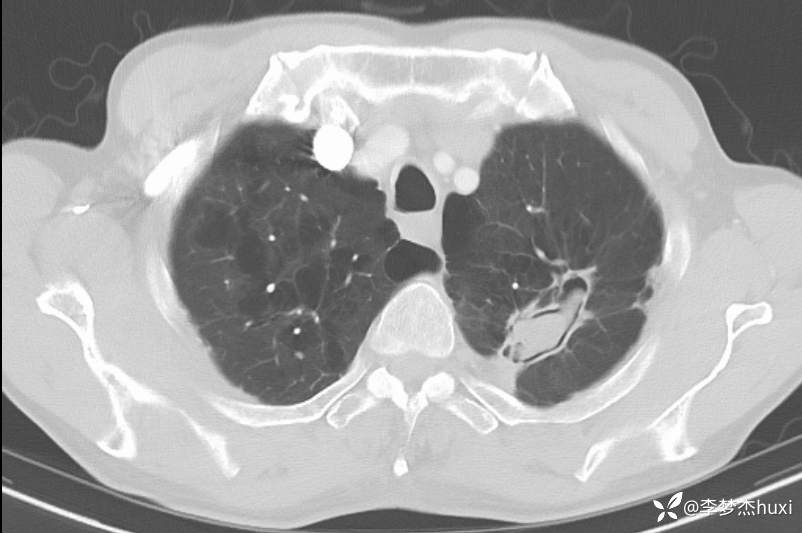

1.现病史:患者老年 男,患者于入院前7天“感冒”后出现咳嗽、咳痰,为白痰,不易咳出,伴胸闷憋气,活动后加重,病初发热,最高达38.0℃,无胸痛,无咯血,无腹痛、腹泻,无恶心、呕吐,无尿频、尿急、尿痛,院外给予口服药物(自诉口服药物,具体药物名称不详)治疗,病情无明显好转,6-13于我院门诊查胸部CT:左肺上叶软组织密度影-性质待定,双肺炎症,双肺气肿,双肺大泡,双肺部分实性结节-炎症?双肺实性结节,主动脉及冠状动脉钙化,双侧胸膜局限性增厚;肝脏多发囊性病变。6-14查胸部增强CT:左肺上叶空洞-真菌感染?占位不除外;双肺炎症,双肺气肿,双肺大泡,双肺部分实性结节-考虑炎症,双肺实性结节,主动脉及冠状动脉钙化,双侧胸膜局限性增厚;肝脏多发囊性病变;今日为进一步诊治来我院;门诊以“肺空洞”收入院。